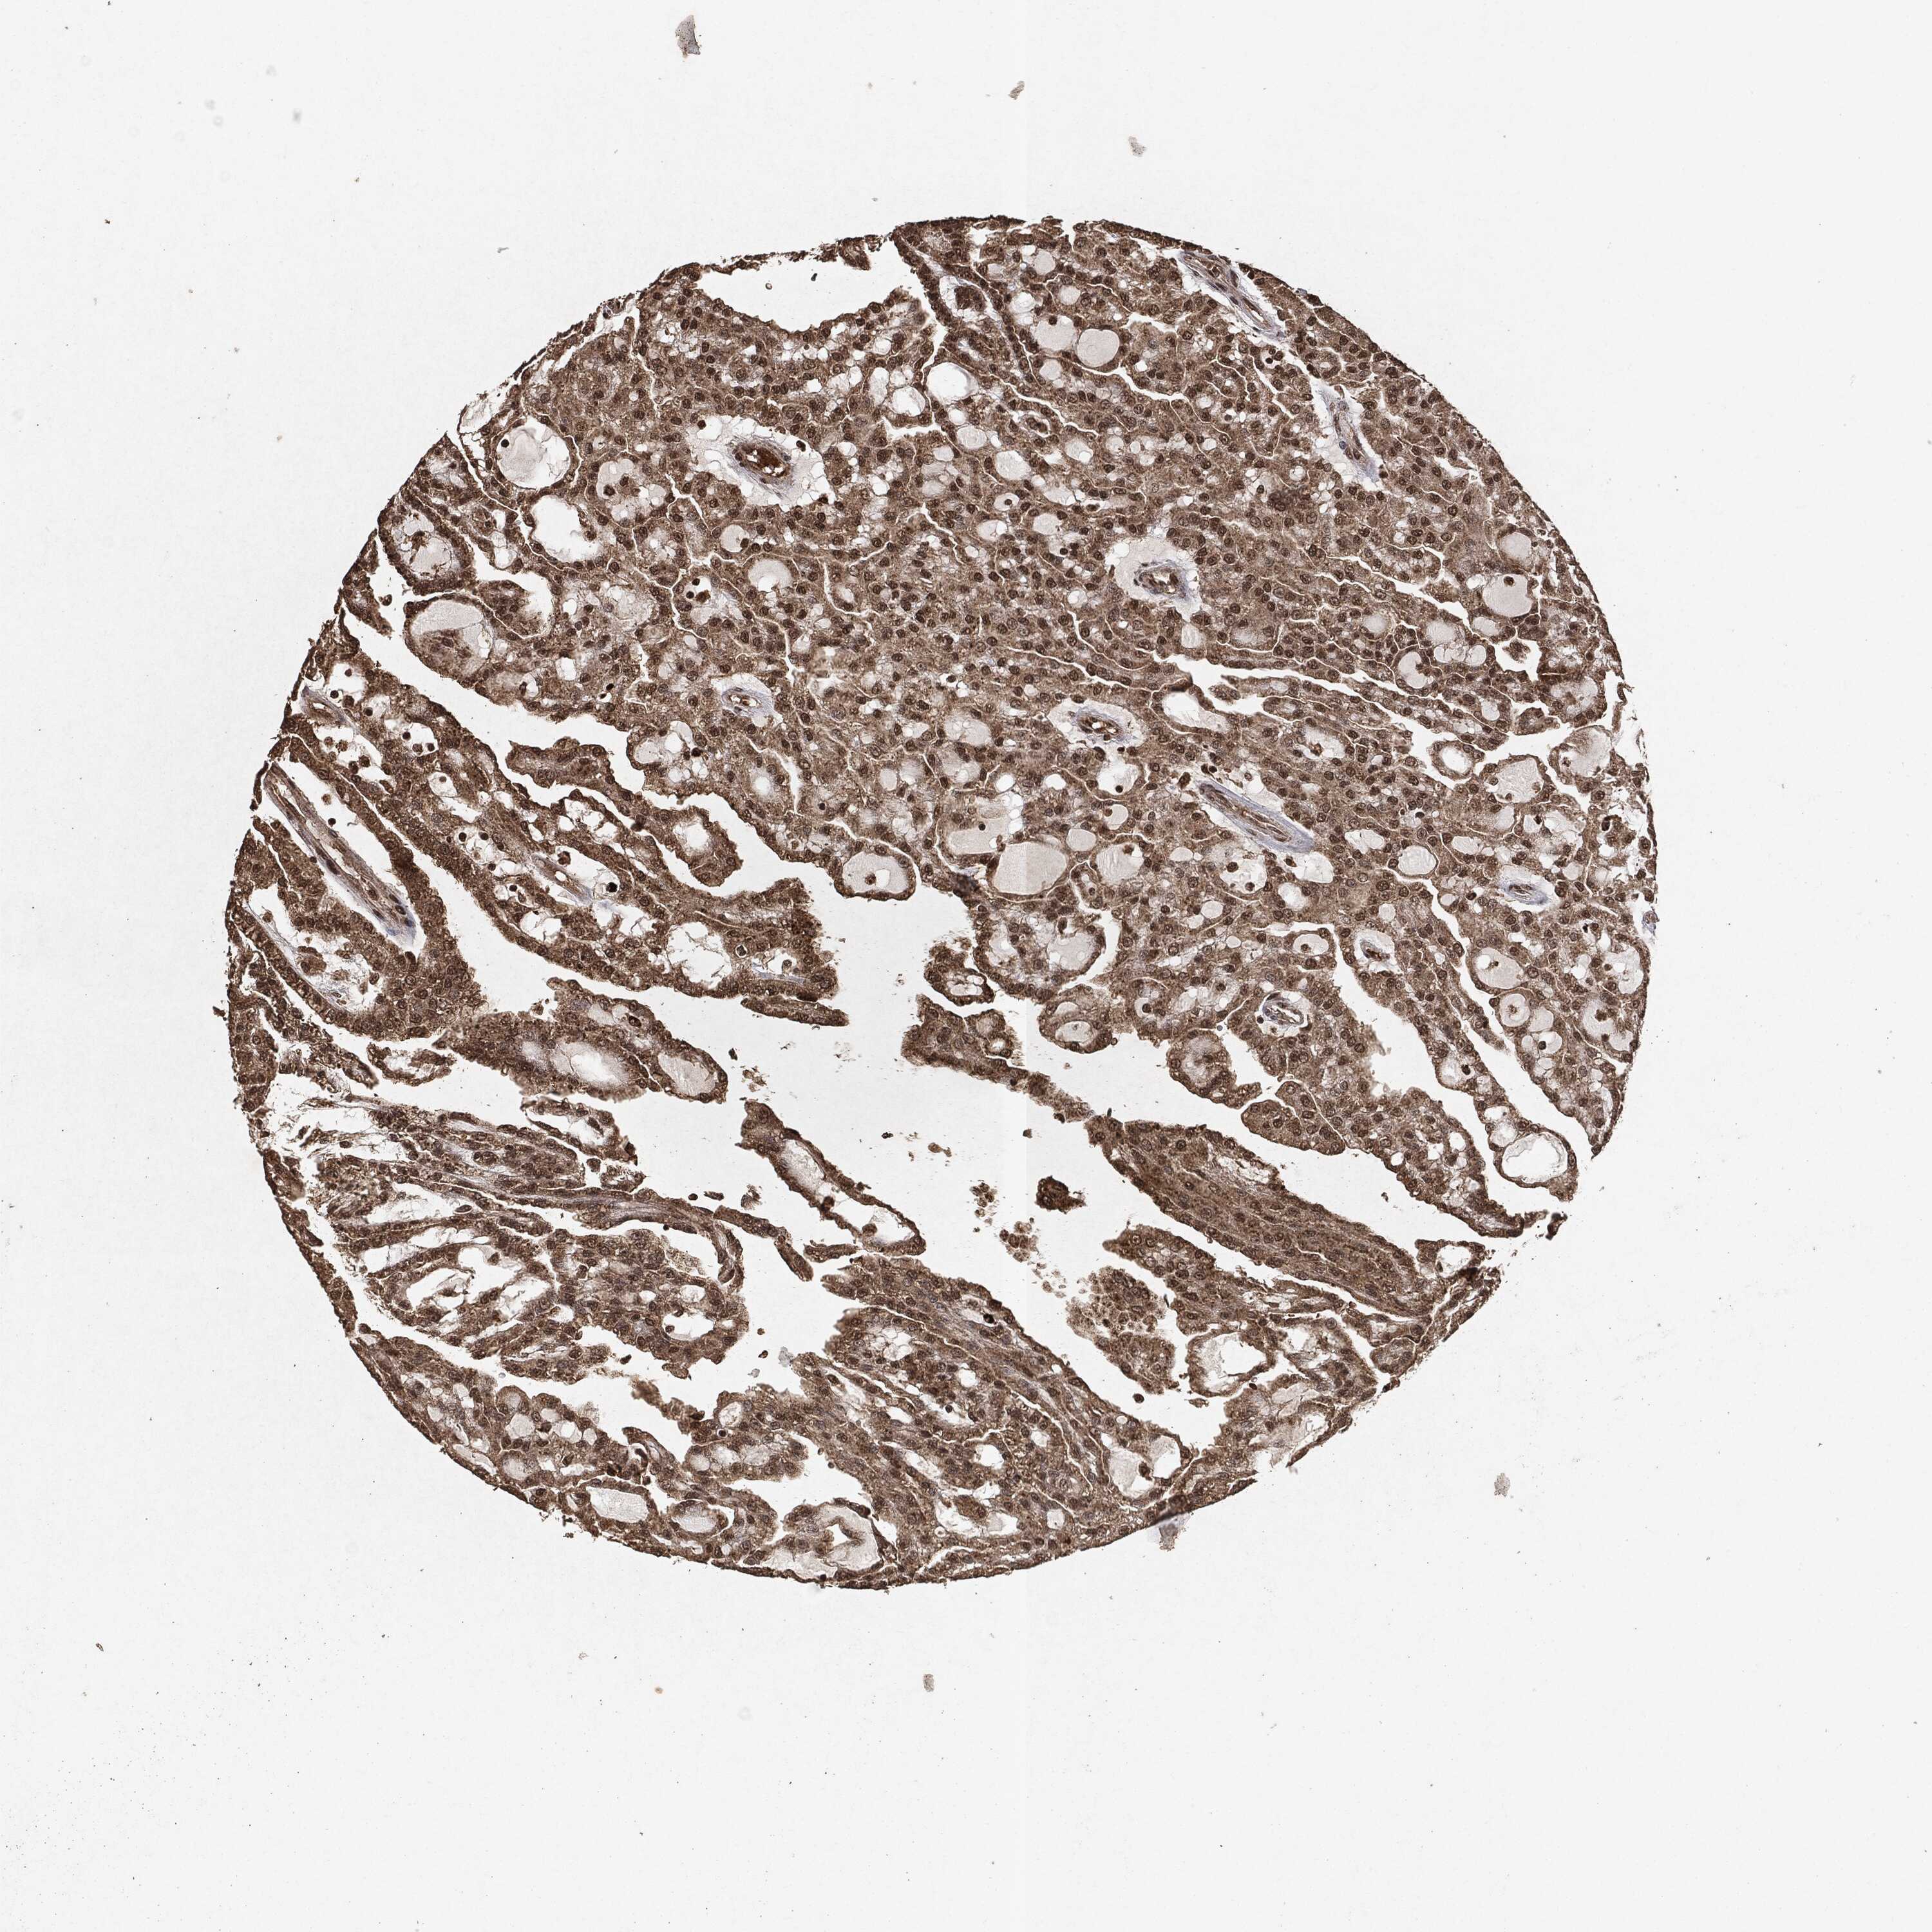

KIDNEY RENAL CLEAR CELL CARCINOMA (TCGA) - Interactive survival scatter ploti

The Survival Scatter plot shows the clinical status (i.e. dead or alive) for all individuals in the patient cohort, based on the same data that underlies the corresponding Kaplan-Meier plots. Patients that are alive at last time for follow-up are shown in blue and patients who have died during the study are shown in red.

The x-axis shows the expression levels (FPKM) of the investigated gene in the tumor tissue at the time of diagnosis. The y-axis shows the follow-up time after diagnosis (years). Both axes are complimented with kernel density curves demonstrating the data density over the axes. The top density plot shows the expression levels (FPKM) distribution among dead (red) and alive patients (blue). The right density plot shows the data density of the survived years of dead patients with high and low expression levels respectively, stratified using the cutoff indicated by the vertical dashed line through the Survival Scatter plot. This cutoff is automatically defined based on the FPKM cutoff that minimizes the p-score. The cutoff can be changed by dragging the vertical line or by entering a cutoff value in the square labeled "Current cut-off".

Under the Survival Scatter plot the p-score landscape (black curve; left axis) is shown together with dead median separation (red curve; right axis). Dead median separation is the difference in median mRNA expression between patients who have died with high and low expression, respectively. It is calculated as follows: median FPKM expression of dead patients with high expression - median FPKM expression of dead patients with low expression. This is intended to aid the user in visually exploring custom cutoffs and the associated p-scores and dead median separation.

Individual patient data is displayed and can be filtered by clicking on one or more of the category buttons on the top of the page. Categories describing expression level and patient information include: high, low, alive, dead, female, male and tumor stages. The scale of the x-axis can be toggled between linear and log-scale by clicking on the "x log" button. Mouse-over function shows TCGA ID, patient information and mRNA expression (FPKM) for each patient.

& Survival analysisi

Kaplan-Meier plots summarize results from analysis of correlation between mRNA expression level and patient survival. Patients were divided based on level of expression into one of the two groups "low" (under cut off) or "high" (over cut off). X-axis shows time for survival (years) and y-axis shows the probability of survival, where 1.0 corresponds to 100 percent.

EGFR is potential prognostic, high expression is favorable in Kidney Renal Clear Cell Carcinoma (TCGA)

Best expression cut offi

Based on the FPKM value of each gene, patients were classified into two groups and association between prognosis (survival) and gene expression (FPKM) was examined. The best expression cut-off refers the FPKM value that yields maximal difference with regard to survival between the two groups at the lowest log-rank P-value. Best expression cut-off was selected based on survival analysis .

When clicking on this number, the vertical dashed line indicating cut-off, the interactive survival plot, and the Kaplan-Meier curve will be adjusted to show results based on the best expression cut-off.

: 29.68

Median expressioni

Median expression refers to the median FPKM value calculated based on the gene expression (FPKM) data from all patients in this dataset. When clicking on this number, the vertical dashed line indicating cut-off, the interactive survival plot, and the Kaplan-Meier curve will be adjusted to show results based on the median expression.

: N/A

Median follow up timei

Median follow up time refers to the median time (years) after diagnosis with this type of cancer, based on clinical data from all patients in this dataset.

P scorei

Log-rank P value for Kaplan-Meier plot showing results from analysis of correlation between mRNA expression level and patient survival.

N/A

5-year survival highi

5-year survival for patients with higher expression than the expression cutoff.

For melanoma and glioma, 3-year survival is shown.

5-year survival lowi

5-year survival for patients with lower expression than the expression cutoff.

TCGA RNA samplesi

RNA-seq data is reported as average FPKM (number Fragments Per Kilobase of exon per Million reads), generated by the The Cancer Genome Atlas (TCGA) .

Normal distribution across the dataset is visualized with box plots, shown as median and 25th and 75th percentiles. Points are displayed as outliers if they are above or below 1.5 times the interquartile range. FPKM values of the individual samples are presented next to the box plot.

Average pTPM 52.9

Number of samples 521